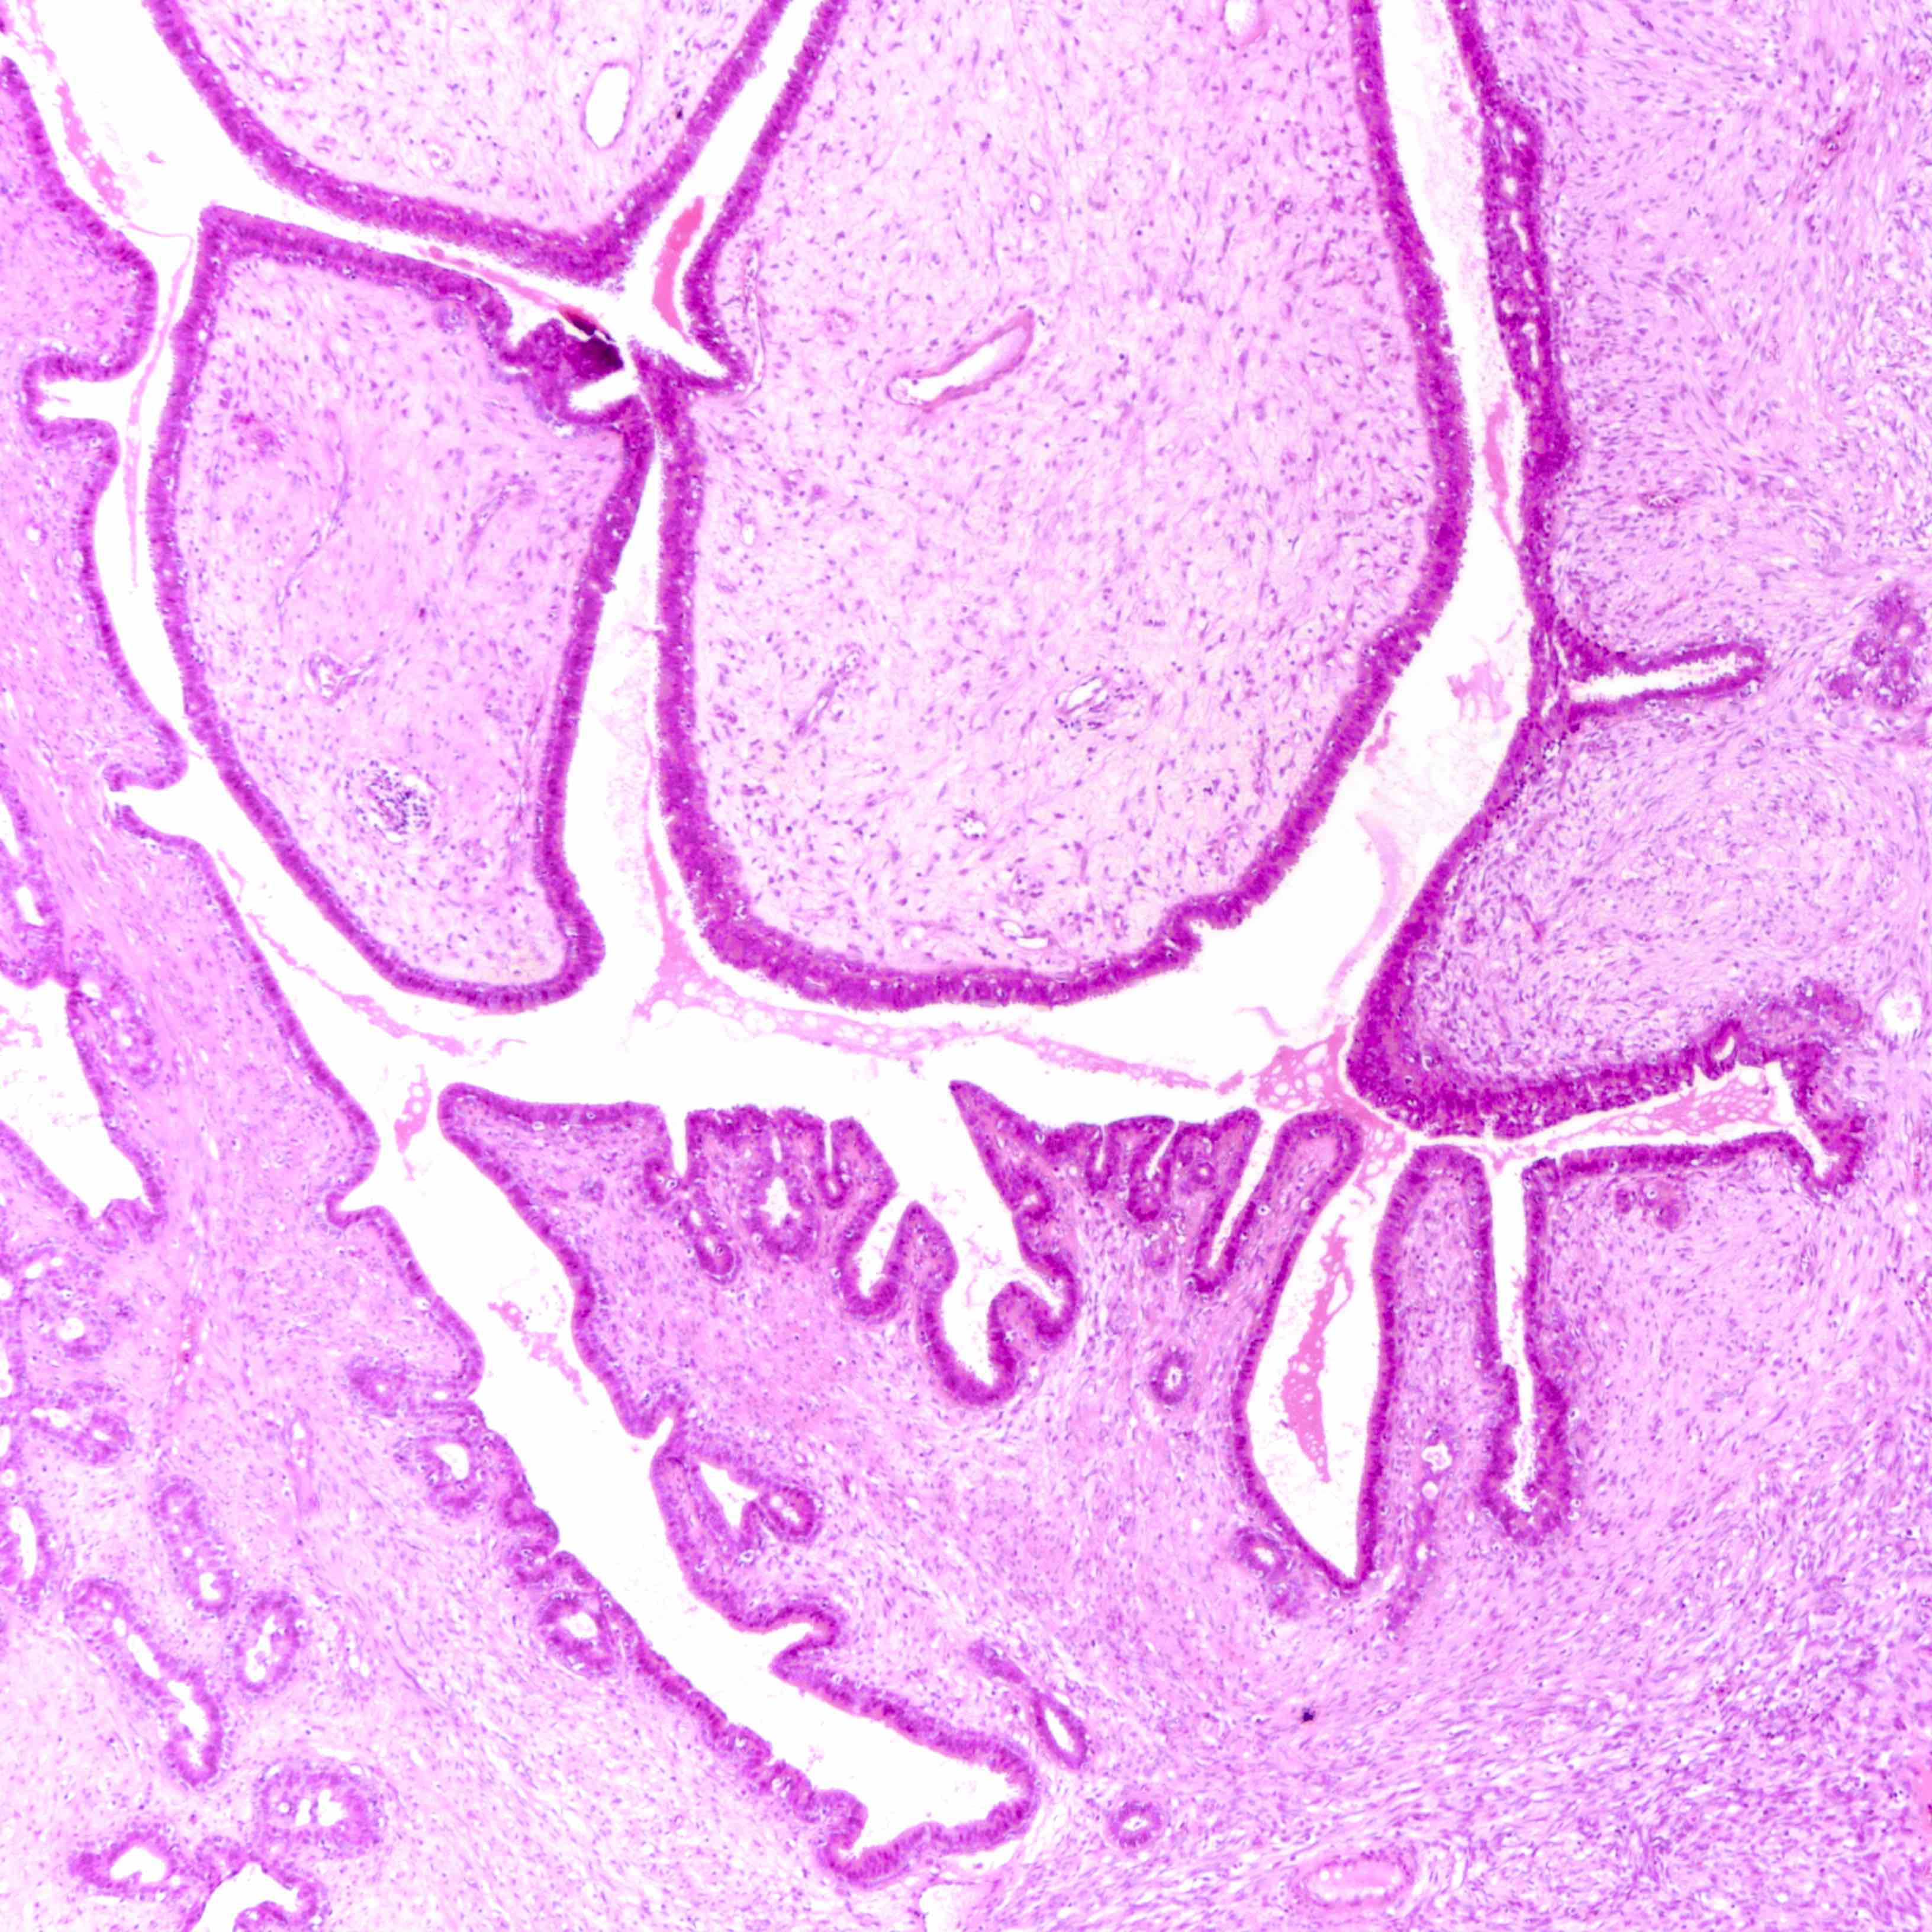

Медицина под микроскопом: гистология и здоровье